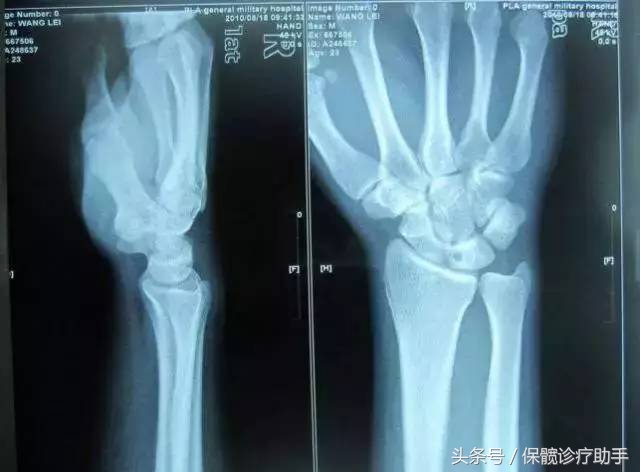

关键词3:腕关节月骨缺血性坏死

腕关节的月骨缺血性坏死,又称金保克(Kienbock)氏病、月骨骨软化症、损伤性骨炎等,也是一种较常见的骨坏死。

病理特征:

骨脱位可分为掌侧和知背侧脱位两种。当月骨完全脱位时,桡月前、后韧带断裂时,虽然已经复位,仍有可能发生腕月骨缺血块死。此外,腕关节反复损伤,使骨营养血管功能紊乱而造成血运障碍,也可引起月骨坏死。

主要表现:

腕部持续性疼痛,同时伴有肿胀。腕正中局部压痛也较明显。纵向叩击及纵向推挤第三掌骨头时,月骨局部亦有疼痛。

此时,腕关节活动明显受限。x线表现为月骨密度增高、囊变、硬化、萎缩、变形而不规则,关节间隙变窄等。